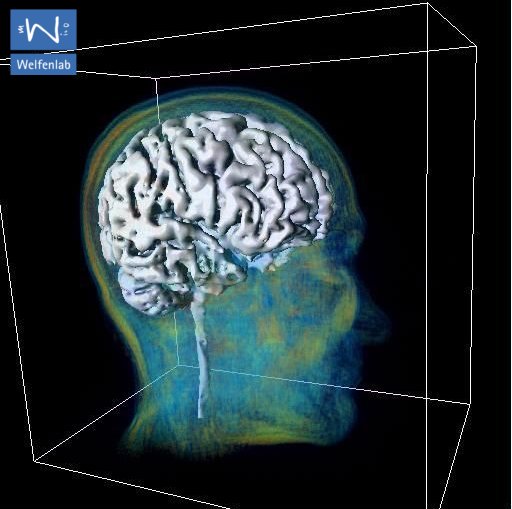

Ein besonders aktueller Schwerpunkt des Welfenlab ist die Visualisierung von Voxeldaten aus dem Bereich der Medizin. Unter einem Voxel kann man sich das dreidimensionale Gegenstück eines Pixels vorstellen. Während ein Pixel (bestehend aus einer x und y Koordinate zusammen mit einem Farbwert) einen Punkt auf einem Computermonitor beschreibt, besitzt ein Voxel zusätzlich eine z-Koordinate. Solche Voxeldaten werden u.a. durch verschiedene bildgebende Verfahren der Medizin gewonnen, z.B. durch Computertomographie (CT) oder Magnetresonanztomographie (MRT). Aus Sicht der Informatik stellt sich die Frage, wie solche Voxeldaten in einer für den Menschen verständlichen Art und Weise dargestellt werden können. Je nach Anwendung kommt es dabei entweder darauf an eine besonders schöne und leicht verständliche Visualisierung zu finden, oder eine möglichst schnelle, interaktive Darstellung bei der sich der Betrachter um das virtuelle Objekt herum oder sogar hindurch bewegen kann.

Beide Anwendungen, Visualisierung und Segmentierung werden am Welfenlab erforscht. Hierfür wurde mit dem Programm YaDiV ("Yet Another Dicom Viewer") eine eigene Software entwickelt, die DICOM Daten einlesen, anzeigen, segmentieren und registrieren kann. Die Evaluation der entwickelten Verfahren erfolgt durch Ärzte an der Medizinischen Hochschule Hannover MHH. Es ist geplant, YaDiV in den kommenden Wochen als OpenSource Software zu veröffentlichen. Mehr über YaDiV ...